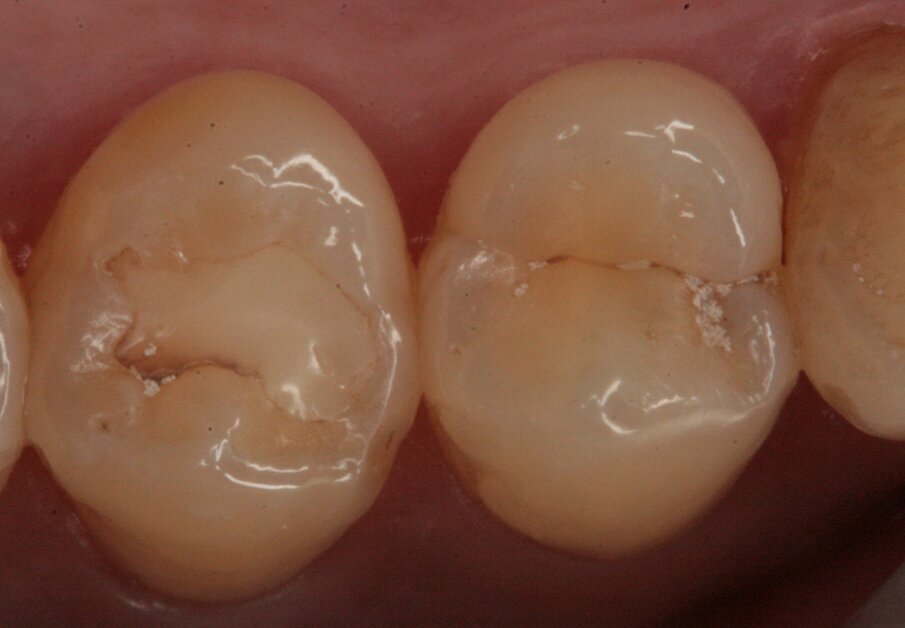

Si è proceduto alla ricostruzione diretta degli elementi 46, 45 e 44 mediante una massa di smalto e una di dentina (Figg. 23-27). L’elemento 47 è stato riabilitato mediante una ricostruzione indiretta in quanto il tessuto dentinale sano residuo era esiguo passando attraverso un build-up pre-protesico per esporre i margini sui quali alloggiare il manufatto (Fig. 28). Il restauro è stato realizzato in resina composita in quanto gli studi longitudinali dimostrano un ottimo follow-up a lungo termine (Fig. 29). La cementazione è avvenuta sempre con isolamento del campo operatorio facendo uso di un cemento duale (Fig. 30).

Fig. 27_Restauro effettuato.